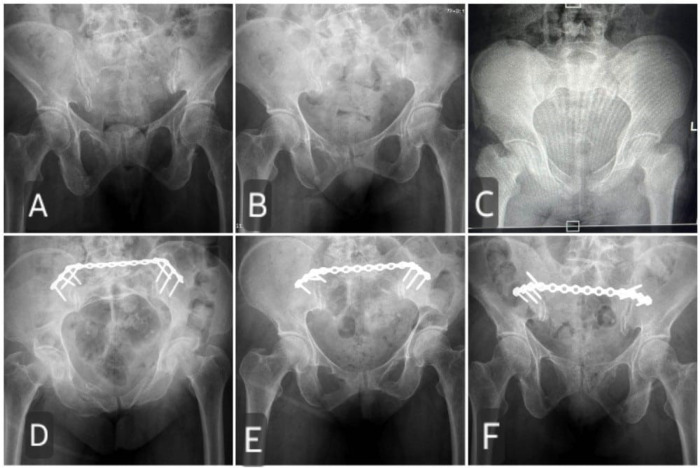

Pelvic ring injuries with rotational and translational instability are complex and often result from high-energy trauma, posing significant challenges in management. Internal fixation has emerged as the preferred approach, with traditional methods such as iliosacral screw fixation exhibiting drawbacks like implant-related morbidity and hardware complications. This paper presents a modified minimally invasive transiliac plating technique aimed at addressing these challenges. The surgical technique involves careful preoperative planning, precise patient positioning, and meticulous exposure of the posterior pelvic structures. Key steps include osteotomy of the posterior superior iliac spine (PSIS), formation of a subcutaneous tunnel, contouring and placement of the plate, and fixation with strategically positioned screws. Additionally, the modified technique incorporates the replacement of the osteotomized PSIS bony fragment, providing secondary stability and minimizing the risk of implant back out. This modification aims to enhance biomechanical stability, reduce implant-related morbidity, and ensure optimal functional outcomes. The technique's efficacy is supported by biomechanical principles and clinical studies, indicating its potential as a promising alternative in the management of unstable pelvic ring injuries. Overall, this modified approach offers improved patient comfort, reduced surgical risks, and enhanced long-term outcomes, contributing to advancements in pelvic ring fracture management.